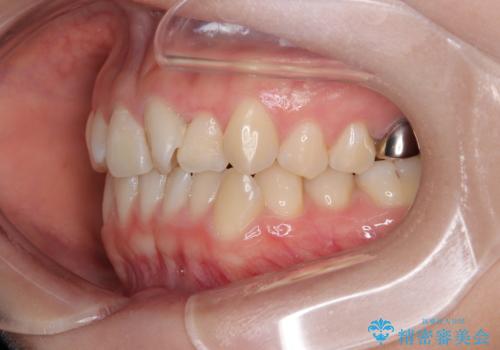

診察の結果、上下の前歯部に**叢生(そうせい/歯のガタガタ・重なり)**が認められました。

特に上の前歯にはねじれや重なりがあり、審美的にも清掃性にも影響している状態でした。

矯正治療期間はわずか10か月と、比較的短期間で終了しました。

前歯のデコボコがなくなり、見た目の印象が大きく変わっただけでなく、歯磨きがしやすくなり、むし歯や歯周病のリスクが大きく減少しました。